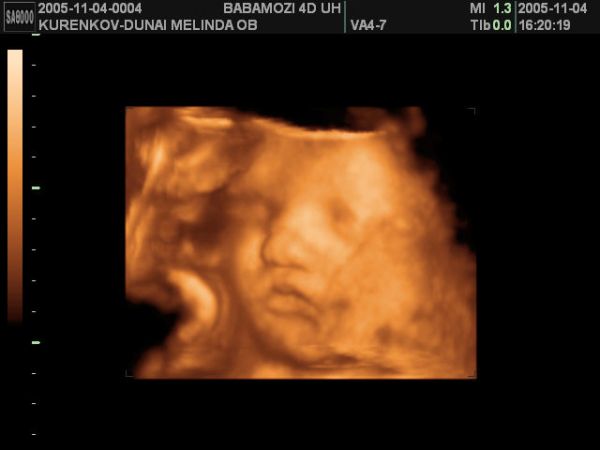

Linácska - tényleg hasonlít rád, nagyon nem semmi !!! Hihetetlen és tökre látszik, hogy kisfiú !